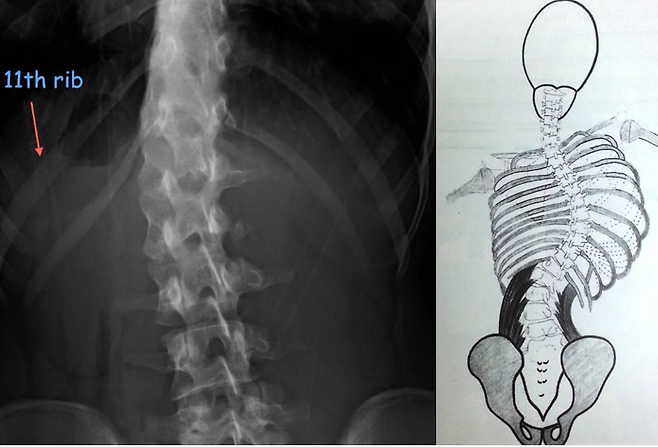

특히 어릴때의 앉을 때의 잘못된 습관으로 인해서 지속된다면이런식으로 허리에 측만증까지 연결이 될 수 있습니다물론 측만증의 원인이 자세만이 다가 아니라선천적인 유전적 요인으로 인해서 생기는 경우가 많이 있지만자세성 측만증도 마찬가지로 무시 하지 못할만큼 많이 있지요